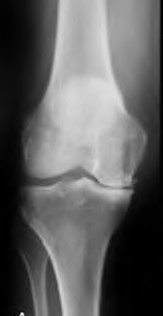

A 67 year-old woman sustained an ACL tear while playing basketball when she was 35 years-old. She has noted progressive leg deformity and episodes of giving way, and now has pain preventing activity. Non-operative management has failed to provide relief. Treatment should consist of?

The radiograph seen in Figure A reveals varus alignment of the knee, with medial tibial deficiency; from this X-ray the patient appears to have unicompartmental arthritis. Treatment options for unicompartmental arthritis include high tibial osteotomy, interpositional arthroplasty, unicondylar knee replacement and total knee replacement. Interpositional arthroplasty became popular in the 1950’s when early outcomes analysis seemed to indicate good results; long term follow up in one study found 0/12 excellent results, with all patients requiring conversion to TKA. This procedure is no longer recommended due to the poor long term outcomes.

While an osteotomy is still used for young and active patients, unicompartmental or total knee arthroplasty have largely replaced this treatment in older patients. Advantages of UKA and TKA include more predictable relief of pain, quicker recovery, and better long-term results. Criteria for UKA include limited unicompartmental disease, no more than a fixed 10 degrees of varus or 5 degrees of valgus deformity from neutral and an intact anterior cruciate ligament with no signs of medial lateral subluxation of the femur on the tibia; this patient is therefore not a good candidate for this procedure.

Total knee arthroplasty can be used to provide predictable pain relief in a patient with unicompartmental and tricompartmental degenerative disease and varus malformation of the knee and for this patient is the best option.